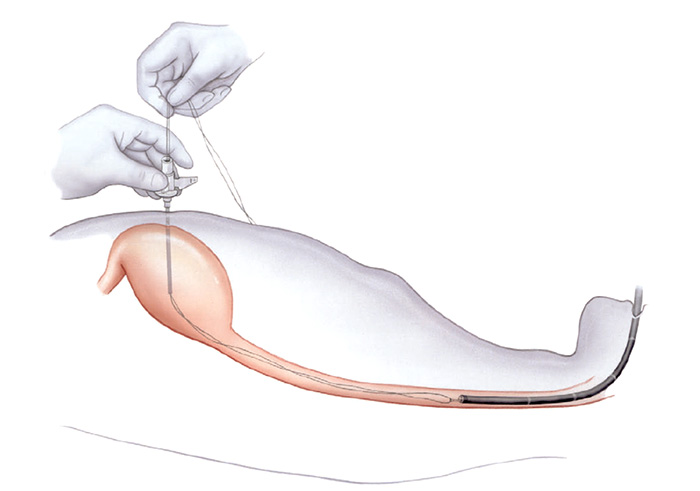

Pacientes que têm o objetivo de emagrecer, podem ter como alternativa a passagem de um balão intragástrico. A passagem do balão é realizada por endoscopia e o procedimento dura cerca de 20 a 30 minutos.

Passagem de Balão Intragástrico

1. O balão intragástrico é introduzido desinsuflado durante a endoscopia e colocado no estômago.

2. Um líquido azul (azul de metileno diluído em soro fisiológico) é colocado dentro do balão através de uma válvula. O volume varia entre 500-700 ml.

3. O aparelho de endoscopia é removido e o balão intragástrico pode ser deixado por um período de até 6 meses.

Pacientes que têm o objetivo de emagrecer, podem ter como alternativa a passagem de um balão intragástrico. A passagem do balão é realizada por endoscopia e o procedimento dura cerca de 20 a 30 minutos.

Passagem de Balão Intragástrico

1. O balão intragástrico é introduzido desinsuflado durante a endoscopia e colocado no estômago.

2. Um líquido azul (azul de metileno diluído em soro fisiológico) é colocado dentro do balão através de uma válvula. O volume varia entre 500-700 ml.

3. O aparelho de endoscopia é removido e o balão intragástrico pode ser deixado por um período de até 6 meses.